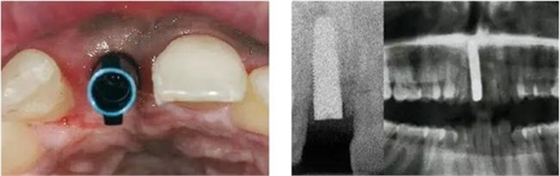

圖4、植入的種植體,初始穩(wěn)定性很好,由于骨缺損范圍大,選擇潛入式愈合。

圖5、種植體完全位于拔牙窩骨壁包圍的范圍內,距離唇側骨板至少2mm。

圖9、種植體植入5個月:種植體到唇側骨板的距離仍然大于2mm,這對于形成長期穩(wěn)的美學效果有很重要的作用。